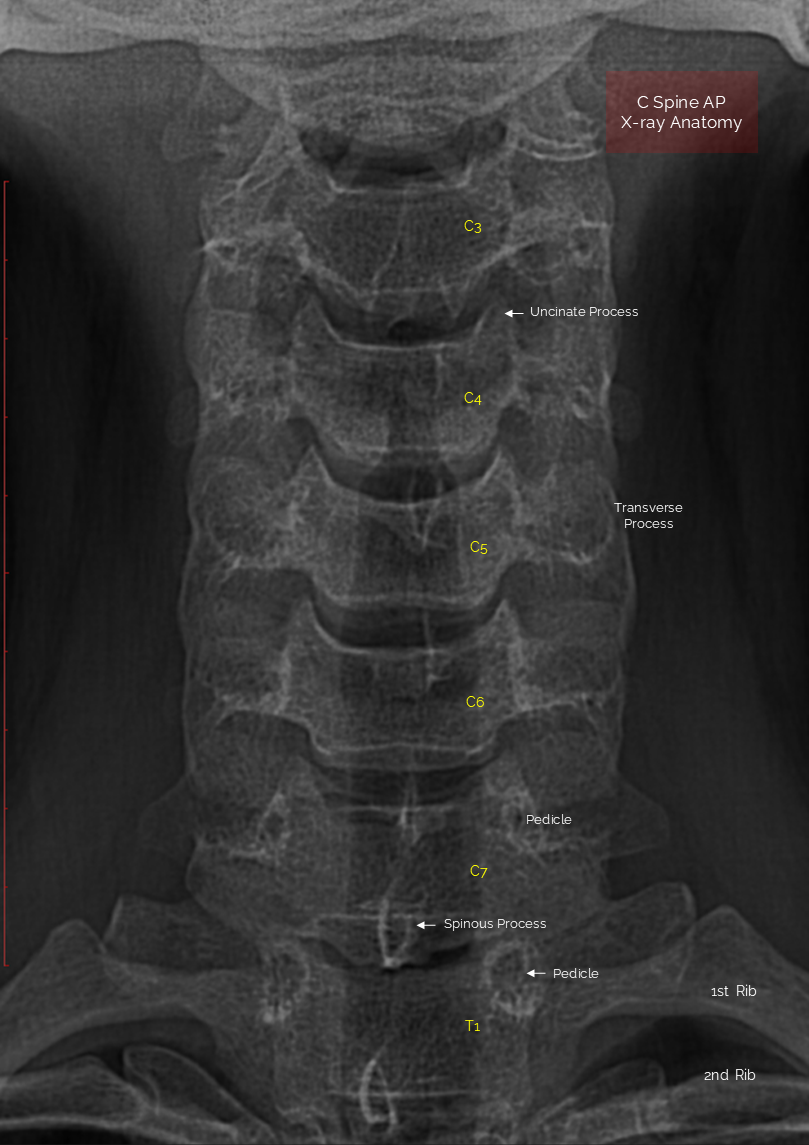

Editorial/Radiography C spine AP by AR Manager 2025. 12. 26. 공유하기 게시글 관리 Acupuncture Radiology 관련글 L spine AP [X-ray anatomy ] Shoulder Detailed MRA of Willis Circle knee MRI anatomy [Coronal, T1]